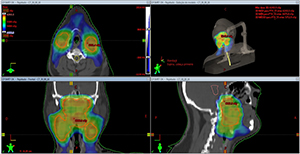

Através de uma tecnologia chamada IMRT (do inglês intensity modulated radiation therapy) foi possível comprovar a segurança do tratamento, que passou a ter duração de apenas 4 semanas, ao invés de 7, e resultados expressivos à doença. Pioneiro no Brasil, o estudo também foi o primeiro no mundo a usar cisplatina (quimioterapia mais recomendada para se associar à radioterapia nesta doença).

De acordo com o coordenador científico do departamento de radioterapia do Hospital de Amor, Dr. Alexandre Arthur Jacinto, mais de 160 pacientes em tratamento de câncer de cabeça e pescoço na instituição já foram beneficiados com a radioterapia acelerada. “A partir deste método, abre-se um novo potencial de estudo em câncer de cabeça e pescoço e uma mudança no padrão de tratamento para este tipo de doença”, afirmou.